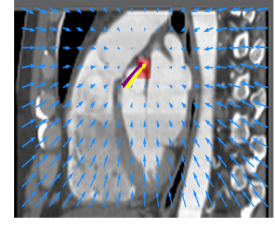

Finally, the proposed network was evaluated for the detection of five additional landmarks: the left coronary ostium, the bifurcation of the LM into the LAD and the LCx, and the origin of the left, non-coronary, and right aortic valve commissures (see Fig. 2). Fig 3 shows vector fields visualizing the predicted displacement vectors in three viewing planes in an image from the test set (for more results, see Appendix). Table 3 lists the Euclidean distance errors between the predicted landmark locations and the reference landmark locations. In addition, box-and-whiskers plots are shown in Fig 4. The best results were obtained for the origin of the right aortic valve commissure. Detection of the origin of the left aortic valve had the most narrow distribution. Outliers were seen during detection of the right ostium, the bifurcation of the LM, and the origin of the non-coronary, and the left aortic valve commissure.

Refer to caption Refer to caption Refer to caption

Figure 3: Vector fields visualizing the predicted displacement vectors in the axial, coronal, and sagittal plane in an image from the test set where detection of the right coronary ostium was performed. The magnitudes of the vectors should point at the right ostium, but they are rescaled for visualization purposes. The red squares indicate posterior probabilities larger than 0.5, obtained by the classification network for image patches. Reference and computed landmark annotations are indicated with a yellow and purple arrow, respectively.